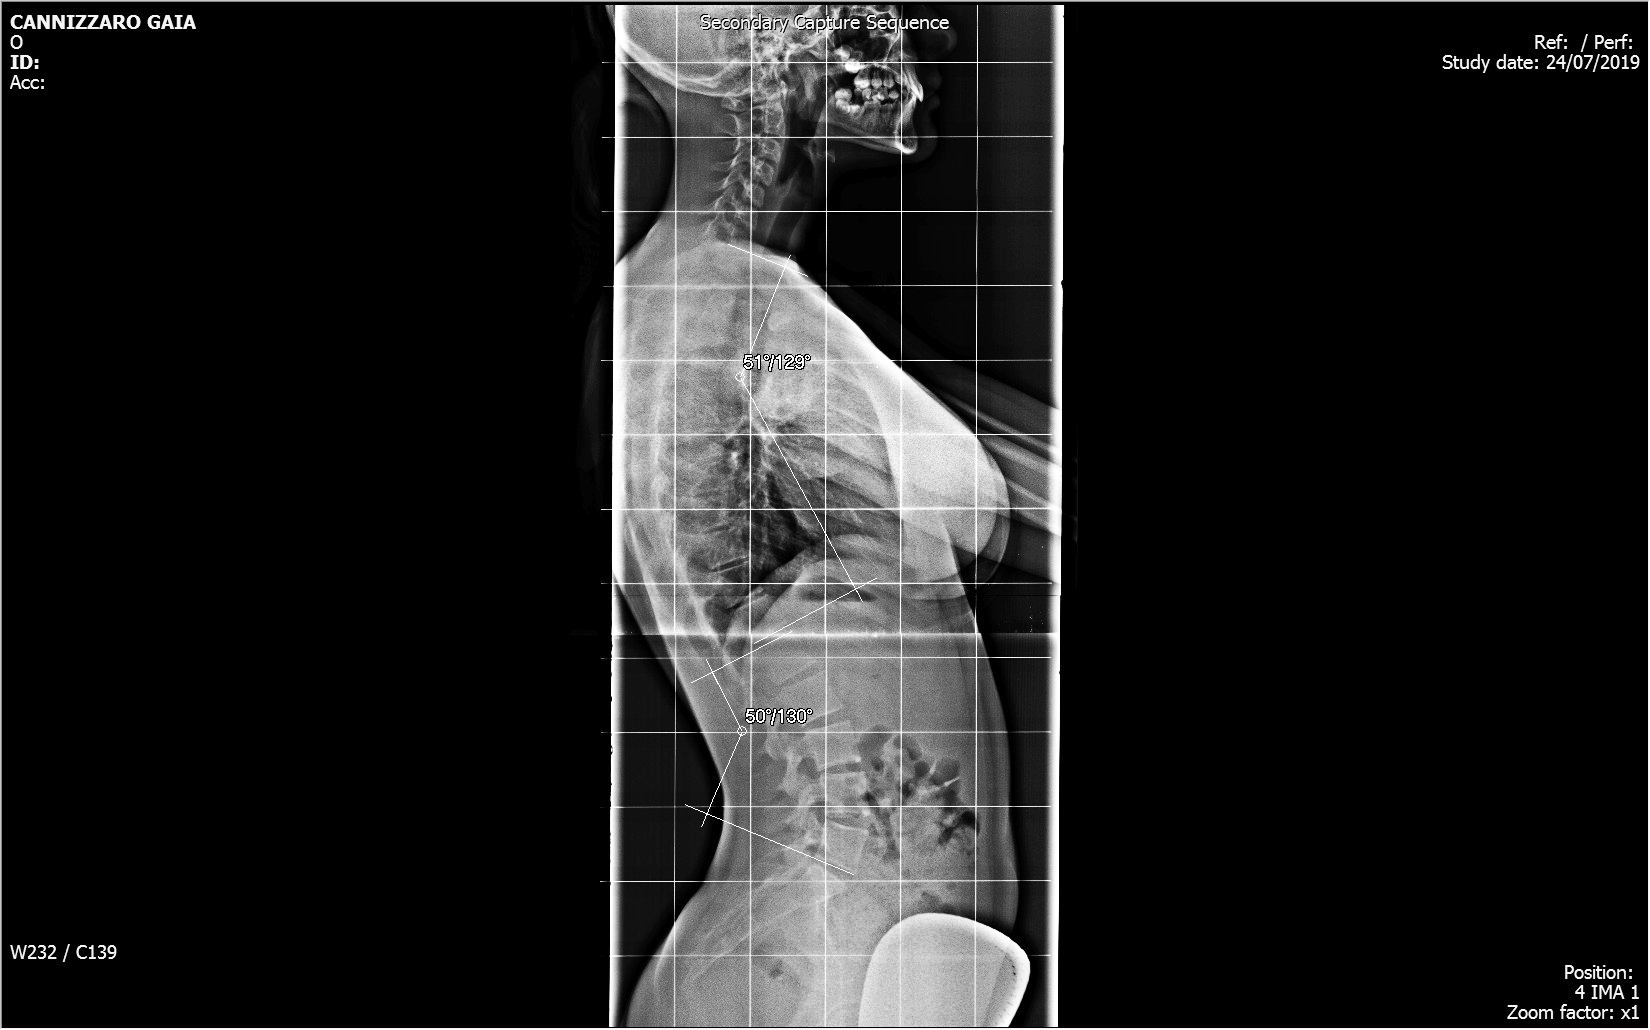

Nel Centro di Radiologia Muglia - Rago - Scaletta si eseguono tutti gli esami di routine dello scheletro, degli organi toraco-addominiali e gli esami contrastografici per lo studio della patologia intestinale ed in particolare la videofluorografia delle vie digestive superiori. La struttura si avvale di apparecchiature moderne e all’avanguardia, che ne fanno un innovativo centro di radiologia digitale a Bagheria e nei comuni limitrofi.

Il centro di radiologia è dotato di un sistema wireless per l'invio immediato delle immagini radiografiche ad un computer, mantenendo una qualità elevata ed evitando superflue esposizioni dei pazienti ai raggi X.

Tutte le immagini acquisite, trattate con un sofisticato post processing, vengono registrate su un supporto digitale (DVD).

Il personale medico è altamente specializzato anche per l’esecuzione degli esami pediatrici con l’uso, ai fini diagnostici, della dose minima di radiazioni ionizzanti.